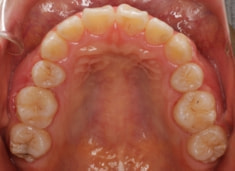

治療前